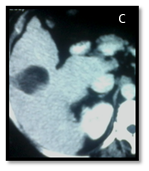

Figure 4A & 4B CT of right hepatic lobe segment V HCC before doing intra-operative Ultrasonography.

Figure 4C & 4D CT of the same lesion after RFA ablation (IOUS changes the decision due to close relation of the mass to the right portal vein.